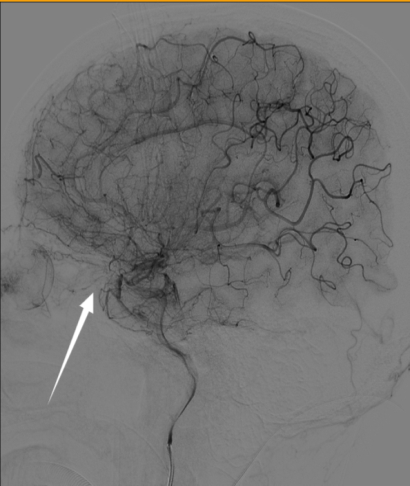

| 眼眶未见造影剂聚集,考虑眼眶尖部占位为肿瘤占位可能性不大 图 4 患者入院第3天脑血管造影 |

患者,72岁女性,因“头痛伴反应差1 d,呕吐1次”入本院神经外科。患者入院前1 d突发头痛,伴意识状态差,不能行走,伴呕吐1次,呕吐物为胃内容物,无抽搐、发热。入院时体温36.5℃,血压187/97 mmHg(1 mmHg=0.133 kPa),神志嗜睡,表情淡漠,GCS评分12分,双侧瞳孔不等大,左侧直径2.5 mm,直接对光反射灵敏,间接对光反射消失,右侧直径4.0 mm,直接和间接对光反射均消失,双侧巴氏征阴性。既往曾出现右侧眼睑下垂,右眼视力变差,1个月前右眼视力丧失,曾在外院诊断为右侧视神经炎性假瘤,有高血压病史,否认手术史及免疫缺陷病史。入院头颅CT提示右侧视神经孔占位性病灶,视神经脑膜瘤可能(图 1)。头颅MR提示:①右侧基底节区、中脑、脑桥、双侧小脑半球多发斑点状/斑片状新鲜脑梗塞灶;②双侧基底节区、放射冠多发斑点状/斑片状脑梗塞灶或缺血变性灶;③右侧眶尖条片状异常信号灶,性质待定(图 2)。经神经内科会诊后考虑急性脑梗死,转入神经内科治疗,神经内科治疗上给予抗血小板、甘露醇脱水降颅内压、营养神经对症处理。患者入院后反复出现发热,发热原因未明,入院第2天经家属同意后行腰椎穿刺留取脑脊液行高通量基因测序。入院第3天,患者病情加重,神志转昏迷,复查头颅提示:①鞍上池、环池、天幕缘见片状稍高密度,考虑蛛网膜下腔出血。脑干、左侧小脑半球见斑片状低密度灶,范围大致如前,考虑脑梗塞,脑干片状低密度灶密度更低,请结合临床;②脑白质病变,脑萎缩,同前;③右侧眶尖部见片状软组织密度影,大小约16 mm×9 mm,性质待定,同前片,建议MR平扫+增强检查协诊(图 3)。考虑蛛网膜下腔出血合并脑室系统扩张,转神经外科急诊行脑室外引流+全脑血管造影术,脑血管造影未见脑动脉瘤及畸形改变(图 4)。术后转入ICU监护治疗,转入ICU后脱水降颅内压、抗感染、脑保护、预防脑血管痉挛等治疗。患者术后出现双侧瞳孔散大,复查头颅提示蛛网膜下腔出血较前增多,双脑室积血、积气,脑干、左侧小脑半球见斑片状低密度灶。入院第4天,脑脊液高通量基因检测结果报告为烟曲霉感染,脑脊液及血液半乳甘露聚糖检测(GM试验,金域)结果分别为6.19/1.42,阳性。综合病史、CT及MR结果,临床诊断为脑烟曲霉感染,改用伏立康唑注射液积极抗真菌治疗,白蛋白联合激素脱水减轻脑水肿、尼莫地平抗脑血管痉挛及脑保护等综合措施。患者体温热峰下降,但持续深昏迷,神经反应差,入院第7天家属放弃治疗出院。

脑曲霉菌感染合并蛛网膜下腔出血较为少见,文献报道多为个案[8]。本例患者肺部及鼻窦部菌未发现曲霉菌感染临床表现以及影像学表现,但头颅CT可见右侧蝶窦外侧骨质缺失,临近眶尖见软组织团块,软组织团块与视神经、眼肌分界不清。MRI见右侧眶尖见软组织团块,T1WI呈等/高信号,T2WI呈等/高信号,DWI呈等/高信号,ADC呈等/高信号,行脑血管造影时未见眼眶有造影剂聚集,结合患者入院2月前在外院发现右侧视神经孔占位性病变并行激素冲击治疗,因而,临床高度考虑患者右侧视神经孔曲霉菌感染,经激素冲击治疗后此位置的直接蔓延导致颅内曲霉菌感染。遗憾的是,入院后患者病情变化迅速,未能获取右侧视神经孔活检进一步明确诊断。尽管在入院第4天明确脑曲霉菌感染,并给予伏立康唑注射液积极抗真菌治疗,但患者病情进展迅猛未能获得良好预后。本例患者急性多发脑梗死及蛛网膜下腔出血考虑与烟曲霉侵犯嗜血管性有关,颅内组织缺血缺氧性坏死,造成脑血管意外的发生,而曲霉菌引起的变态反应加重或导致了恶性脑水肿,最终造成患者不良预后。